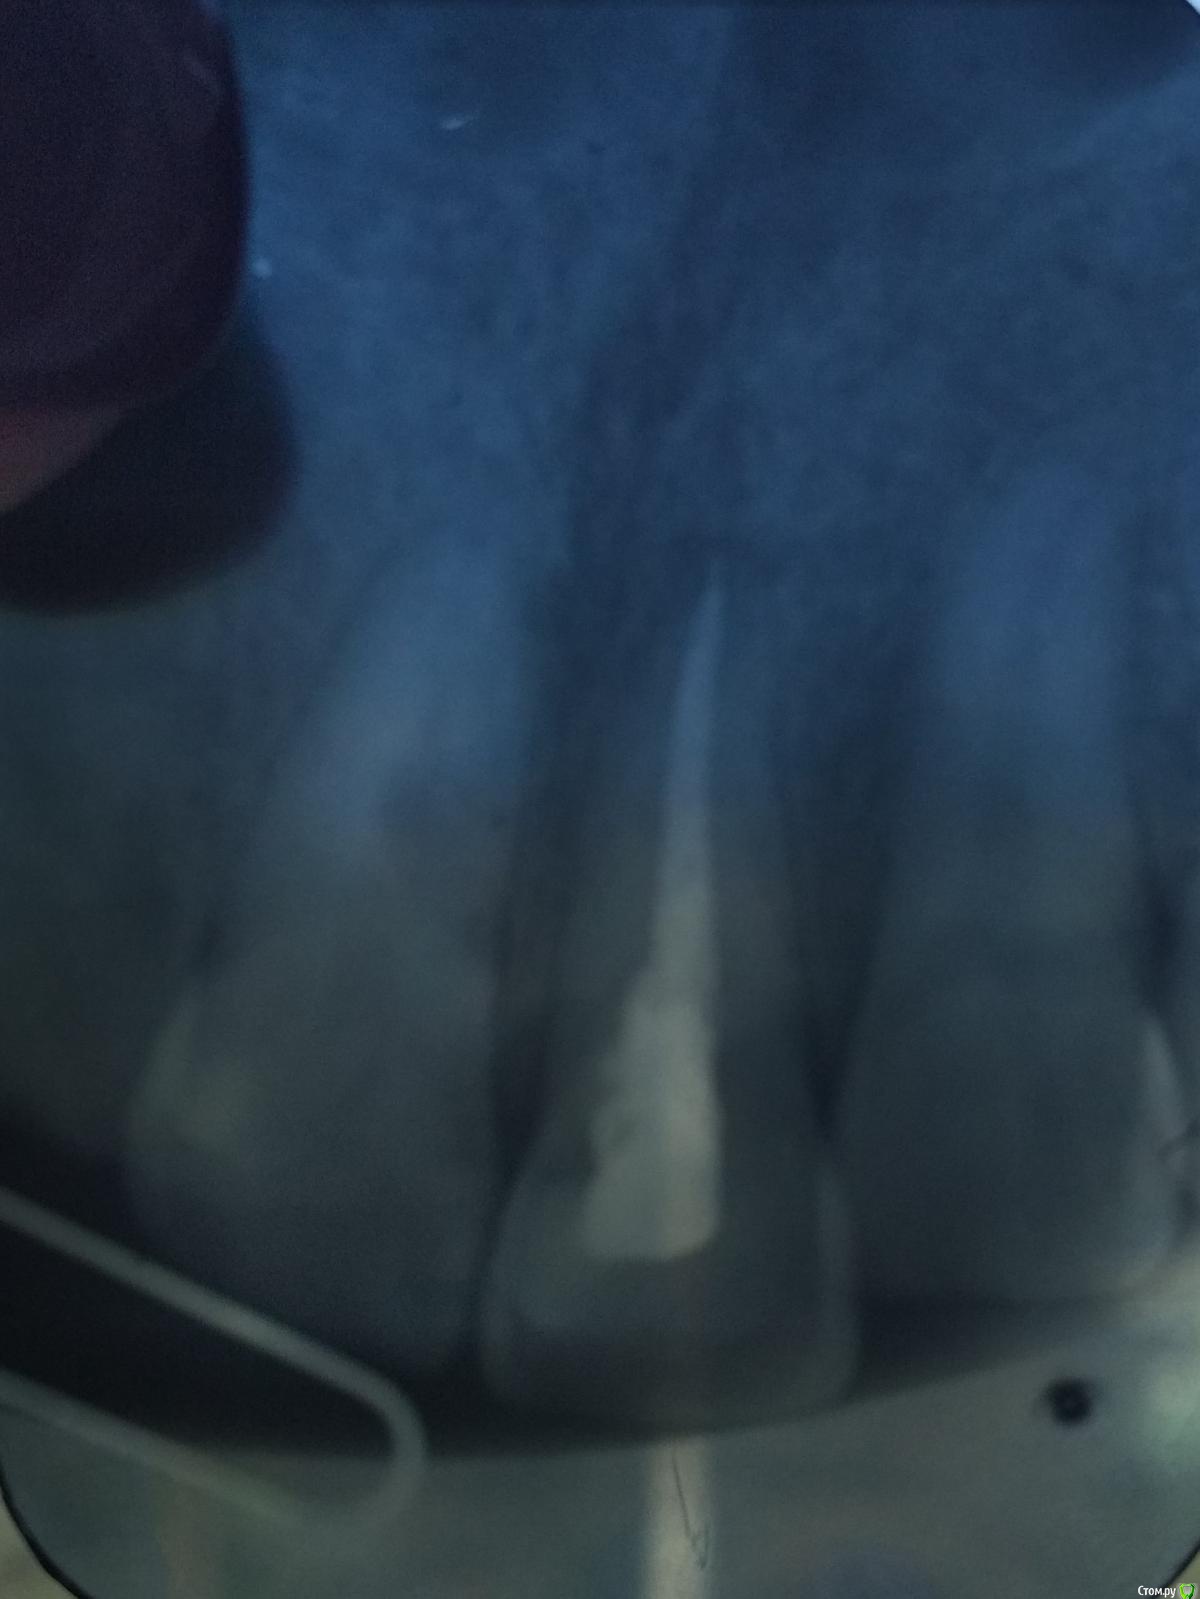

krokomot Опубликовано 23 апреля, 2019 Поделиться Опубликовано 23 апреля, 2019 Боль и припухлость это результат инструментальной обработки, скорее всего часть дентинных опилок попали за верхушку корня. Отсюда и воспаление. Я бы сделал качественный снимок на визиографе, что бы оценить качество пломбировки, по этому снимку канал запланирован приемлемо. Но вы должны понимать, что снимок не отображает всех особенностей канала, могут быть дополнительные ответвления. Обработать их не у всех получается. Требуются контрольные снимки через 3, 6, 12 месяцев. Ссылка на комментарий

krokomot Опубликовано 24 апреля, 2019 Поделиться Опубликовано 24 апреля, 2019 Скажите, пожалуйста, все хорошо с качеством пломбировки?по этому снимку качество пломбировки хорошее. 1 Ссылка на комментарий